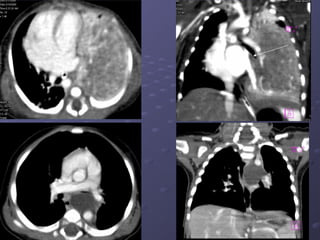

Sau tiêm CQSau tiêm CQ

Chẩn đoán siêu âm + CTChẩn đoán siêu âm + CT :: bất

thường phổi biệt lập bên trái, có

nhánh động mạch nuôi xuất

phát từ ĐMCN.

- Chụp CT scannerChụp CT scanner (++90%): tiêm cản(++90%): tiêm cản

quang, đa dãy, dựng hình MPR, 3D mạchquang, đa dãy, dựng hình MPR, 3D mạch

máu.máu.

. Là khối choán chỗ đậm độ mô mềm,+_. Là khối choán chỗ đậm độ mô mềm,+_

đồng nhất, ++ cạnh sống trái, +_ dạng ‘tổđồng nhất, ++ cạnh sống trái, +_ dạng ‘tổ

ong’, nang khí or mức khí – dịch. Sau tiêmong’, nang khí or mức khí – dịch. Sau tiêm

cản quang, tăng tỉ trọng không đều, thấycản quang, tăng tỉ trọng không đều, thấy

rõ mạch máu nuôi.rõ mạch máu nuôi.

ĐMTT

- Chụp CTscannerChụp CT scanner (++90%): tiêm cản(++90%): tiêm cản quang, đa dãy, dựng hình MPR, 3D mạchquang, đa dãy, dựng hình MPR, 3D mạch máu.máu. . Là khối choán chỗ đậm độ mô mềm,+_. Là khối choán chỗ đậm độ mô mềm,+_ đồng nhất, ++ cạnh sống trái, +_ dạng ‘tổđồng nhất, ++ cạnh sống trái, +_ dạng ‘tổ ong’, nang khí or mức khí – dịch. Sau tiêmong’, nang khí or mức khí – dịch. Sau tiêm cản quang, tăng tỉ trọng không đều, thấycản quang, tăng tỉ trọng không đều, thấy rõ mạch máu nuôi.rõ mạch máu nuôi.